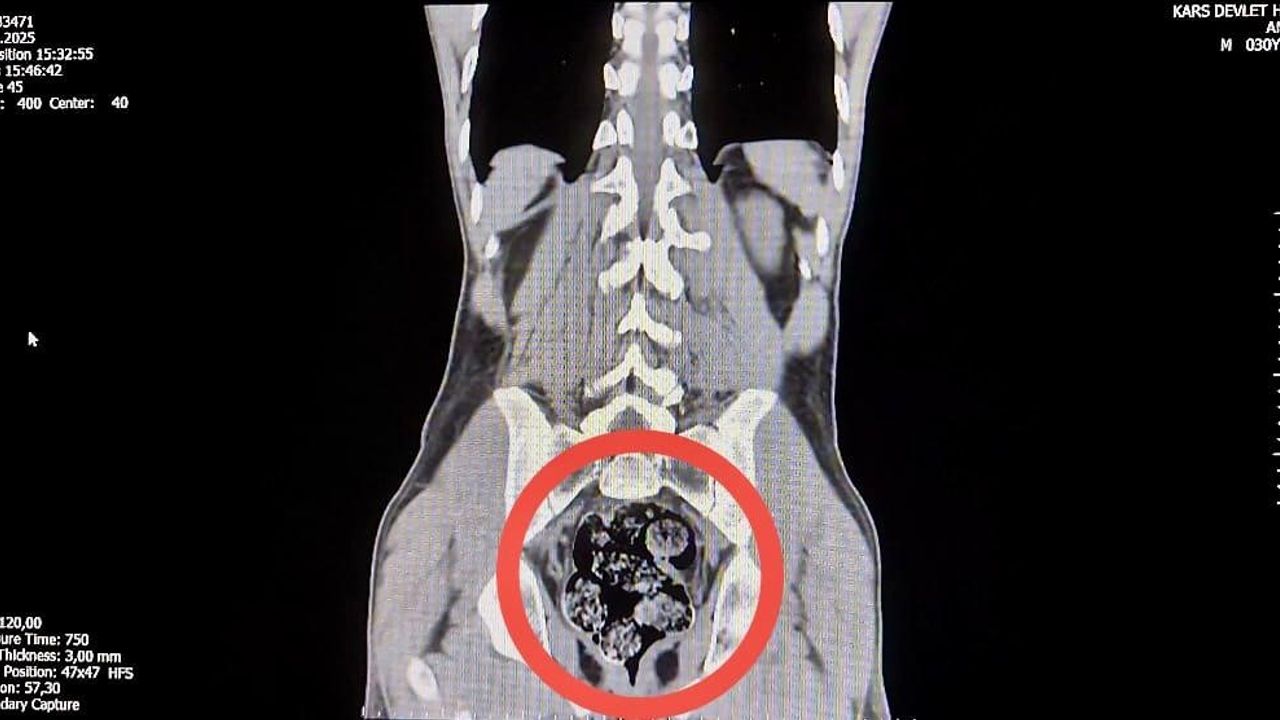

İl Emniyet Müdürlüğü’ne getirilen ve durumundan şüphelenilen kuryelerden Shekarbaghanı, detaylı arama için Kars Harakani Devlet Hastanesi’ne götürüldü. Hastanede yapılan emar ve röntgen kontrollerinde şüphelinin makatında cisim olduğu belirlendi. Yapılan cerrahi müdahalede, şüphelinin makatından 7 parça halinde 203,02 gram metamfetamin çıkarıldı.